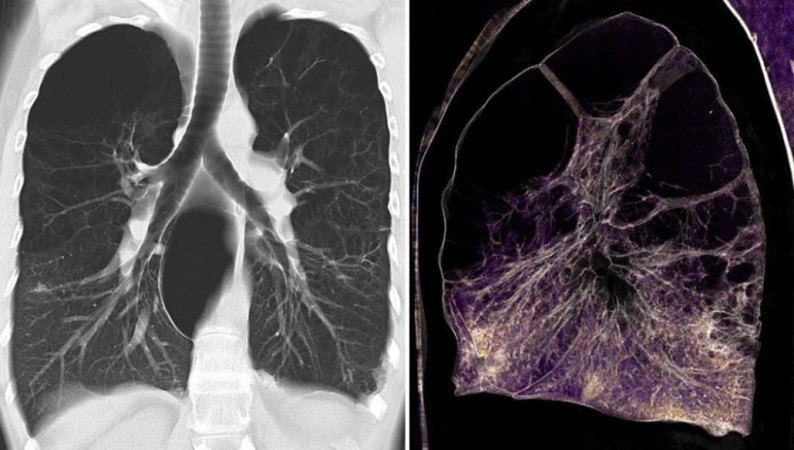

At first, CT scanners were designed to image only the brain. But researchers quickly adapted the technology to take cross-sectional images, or slices, at various points along the body. Then, in the early 1990s, scanners were created in which the X-ray source scanned in a continuous spiral around the body, instead of taking individual cross-sections. That advance allowed a whole organ, such as the lungs, to be imaged in one go.

But the image resolution along the length of the body was still low. CT scanners with multiple rows of X-ray detectors solved this problem by imaging several slices of the body at once along the spiral path.

CT scanner manufacturers kept pushing up the number of detectors, making scanners that could capture more slices at once. When detectors hit 64 slices in the early 2000s, McCollough says, “the real ‘Wow’ happened.” Scans could be fast, high resolution and cover a significant length of the body, all at once. Today, scanners are even more sophisticated, using up to 320 slices.

Finally, the fragile complexity hidden inside the human body — from the intricate webs of blood vessels to the gracefully branching air passages of the lungs to the delicate yet sturdy structure of bone — was there for all to see.

There’s no denying that, when warranted, CT scans are a crucial, lifesaving part of the medical toolkit. Recently, the scans have been in the spotlight for revealing damage done to the lungs by COVID-19 (SN: 4/27/20). The technology seems poised to remain a mainstay of medicine and science in future decades, continuing to scan its way into our hearts, lungs, brains and everywhere else.